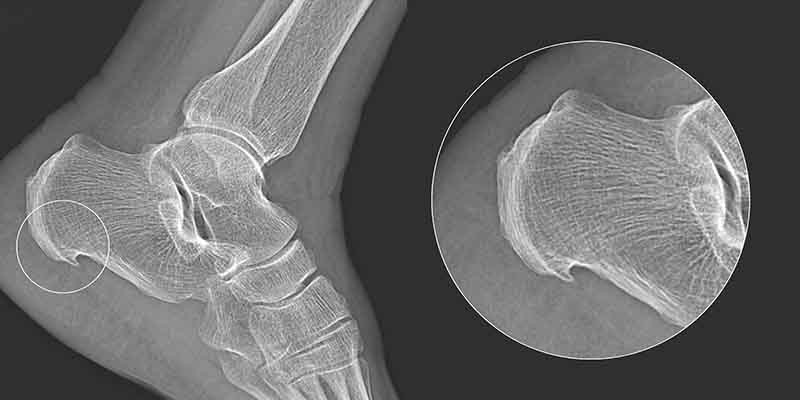

Haglund's disease was first described in 1927 by Patrick Haglund. This condition was initially classified as idiopathic, meaning it has no clear cause, although medical professionals have linked it to several factors. Haglund’s deformity, or "Haglund’s heel," is a condition where an extra bony growth forms on the calcaneus (heel bone), causing irritation and inflammation. This is well illustrated by the X-ray image of a patient’s heel before surgery. Just as people have different nose shapes and sizes, variations in the size and shape of these bones also occur. The protruding bony growth can rub against the Achilles tendon above it, leading to tendon pain. In this case, heel pain at the back is not the result of a single injury but is often related to physical activity and strenuous training (especially running or sports like soccer). However, this is not always the rule, as heel pain can also affect individuals with no connection to sports.

The first symptom is pain at the back of the heel, over the bony prominence, without significant swelling. Early symptoms are mild, leading only to discomfort while walking. Patients report pressure in the rear part of the heel, especially when putting on shoes. Initially, the symptoms are not severe or bothersome enough to prompt a visit to the doctor. This allows the deformity of the heel bone to progress over time. Gradually, these symptoms worsen, leading to noticeable limping while walking. Heel pain most often occurs after physical activity or in the morning but rarely at night. Over time, the heel develops a visible deformity accompanied by painful swelling, as shown in the images. In such an advanced stage of the condition, the calcaneus becomes very painful, especially during dorsiflexion of the foot. A further stage may involve inflammation at the Achilles tendon attachment to the calcaneus.